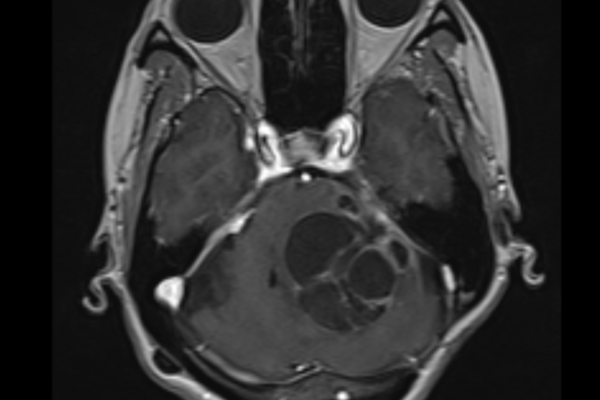

症例 聴神経腫瘍 頭蓋底部

症状について こちらの女性は左の耳が聞こえなくなり病院に受診されました。検査の結果、聴神...